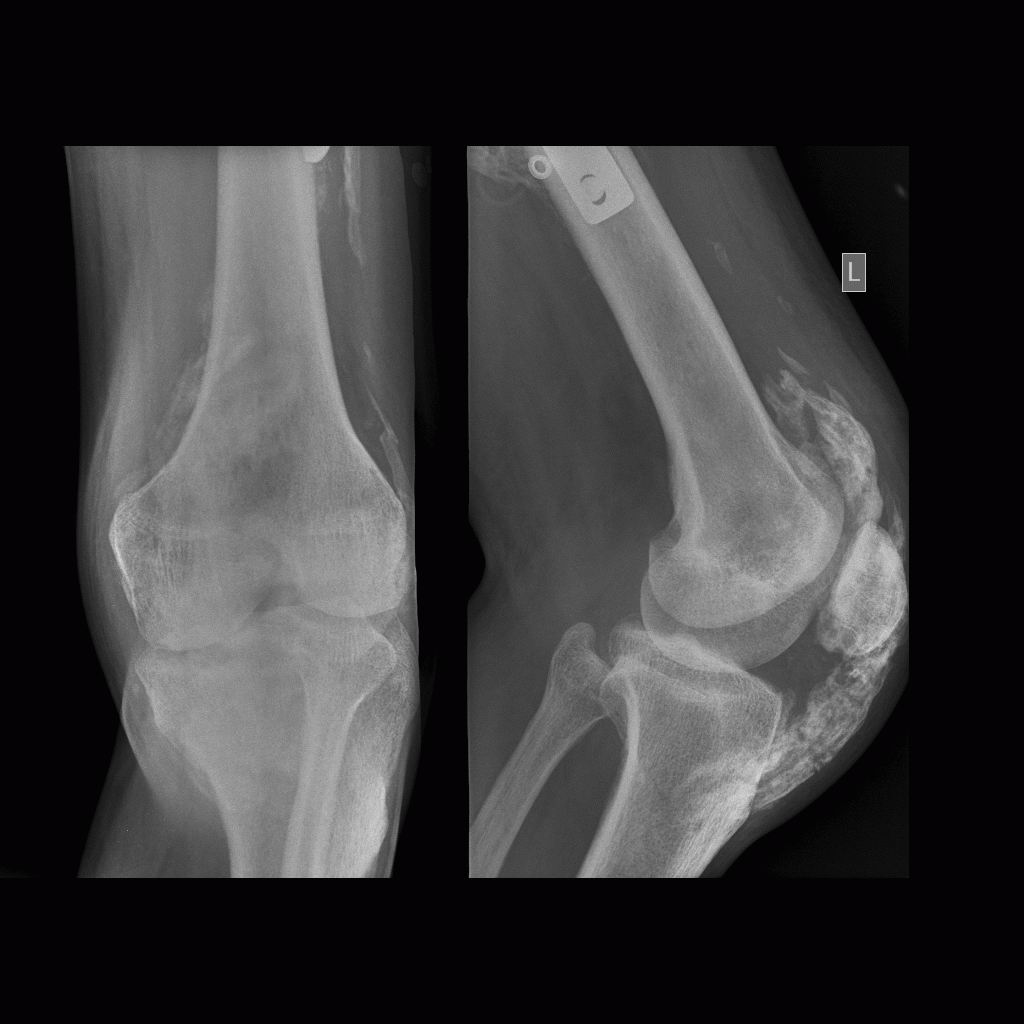

男,三十岁,多处外伤性骨折术后两月余。

骨化性肌炎:原因不明,多于外伤有关。好发于青年男性,多位于受伤部位的四肢深部组织如股四头肌、股内收肌、上臂肌及肘部肌群内,但不局限于肌肉。

临床上多有外伤史,及全身疾患如截瘫、昏迷等。早期局部肿胀、疼痛,可扪及包块,邻近关节活动受限。病理:早期为局部软组织水肿、变性、坏死、肌纤维断裂及原始间叶细胞增生形成肿块,之后肿块变硬,最外层形成成熟的纤维组织和骨组织,肿块不侵犯骨组织,但可与骨皮质相连。

影像表现为初期患处局限性肿胀,肌间隙模糊,密度增高,之后出现絮状钙化影及毛糙不整的网状致密影,邻近骨质可有骨膜反应;中期肿块内出现条状或层状钙化影,边缘部位出现致密骨。后期肿块缩小,与邻骨间以透亮带相隔或紧密相连,肿块内出现高密度钙化及骨结构形成,骨化影大部分沿肌束走行,是其重要鉴别点。需与下列疾病鉴别,1.骨外软组织骨肉瘤 2.骨外软骨肉瘤  3.皮质旁骨肉瘤 4.骨间膜钙化 5.进行性骨化性肌炎及软组织的其他钙化性疾病。

骨旁软组织内见广泛斑片条状密度增高影,考虑外伤性骨化性肌炎。